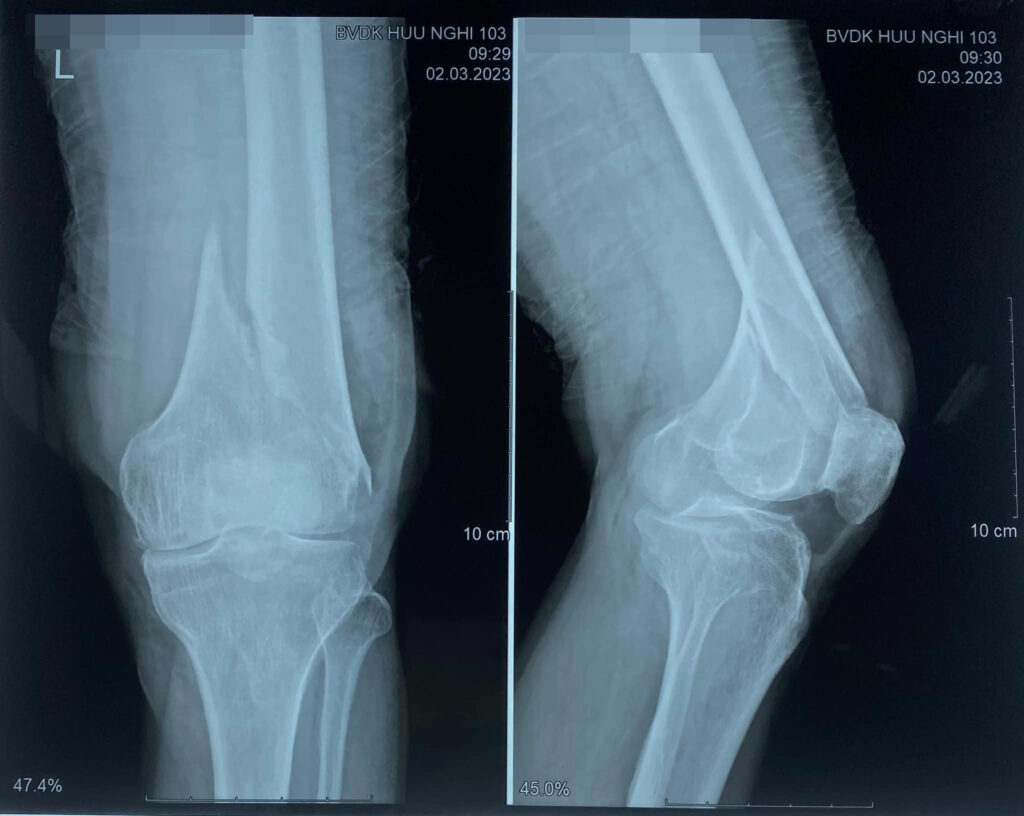

Kết quả sau phẫu thuật kết hợp xương trong gẫy đầu dưới xương đùi bằng nẹp khoá trên bệnh nhân cao tuổi loãng xương.

Gãy đầu dưới xương đùi là một gãy xương lớn, phức tạp, thường ảnh hưởng đến chức năng vận động của khớp gối. Nẹp khóa đầu dưới xương đùi giúp cố định vững chắc ổ gãy theo cấu trúc giải phẫu. Bệnh nhân hài lòng với kết quả điều trị.